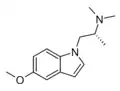

Related compounds

A number of related compounds are known, with a similar structure but having the indole core flipped and/or replaced with related cores such as indoline, indazole, benzothiophene, or benzofuran. These similarly are primarily active as agonists at the 5-HT2 family of serotonin receptors, with applications in the treatment of glaucoma, cluster headaches or as anorectics.

AAZ-A-154 | (2R)-1-(5-methoxy-1H-indol-1-yl)-N,N-dimethylpropan-2-amine | |